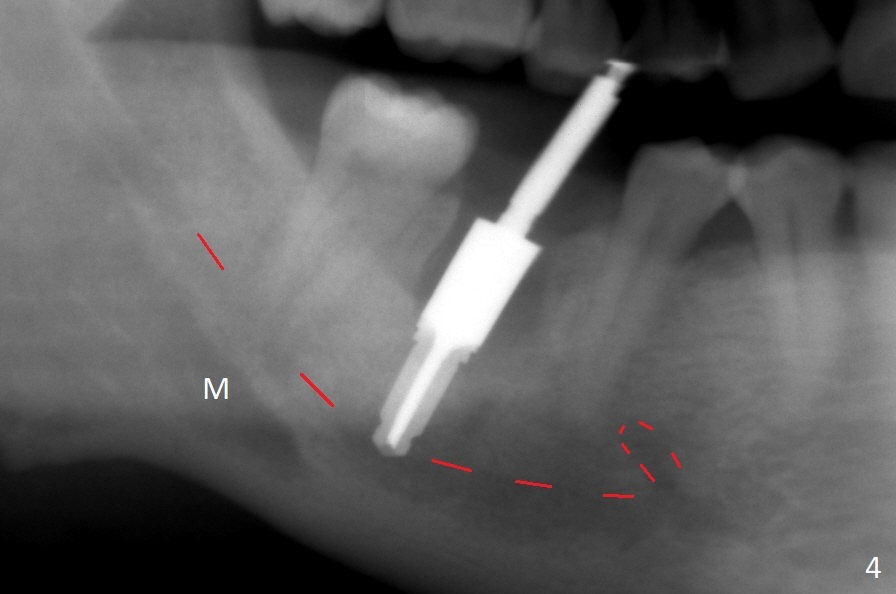

After the tooth #30 is extracted, the socket is 18 mm deep and the lingual plate is 4 mm tall. With hemorrhage, visibility of the socket, especially the bottom, is poor. The septum is almost completely defective. Following removal of the most buccal portion of the septum, osteotomy is initiated as buccal as possible, but it is mesial (Fig.1). In spite of effort to move the osteotomy distal, the osteotomy remains mesial and superficial (Fig.2 with 5 mm tap drill). Pain control is poor with infiltration. It appears that the smaller osteotomy (Fig.2 yellow line) may have extended close to the superior border of the Inferior Alveolar Canal (red line). It appears that there is 8.5 mm bone distal with ~ 2 mm clearance. After mandibular block, a new osteotomy is made distal; when a 3.8 mm drill is being used, there is hemorrhage from the osteotomy with apparent violation of the Canal integrity (Fig.3,4). But hemostasis is achieved with gauze pressure. A 5x13 mm implant is placed superficially (Fig.5) with a trace of the previous osteotomy (yellow line) and deep space created by the mesial osteotomy (*). Apparently the pathological and iatrogenic defects are filled with allograft (Fig.6 *). Guided surgery could have avoided the mesial osteotomy.

Fortunately no paresthesia is reported postop. Why is the Inferior Alveolar Canal not violated? Fig.7 is a coronal section of CBCT taken for a 40-year-old man at the lower 1st molar (at the septum). At the region, the Canal (brown circle) is close to the lingual plate (L). Because of severe bone loss of the lingual plate of this case (Fig.8 *), osteotomy is intentionally created buccal (green). The deep osteotomy may not contact the Canal, while the hemorrhage may stem from the medullary space (M in Fig.4,7). Bone morphology at the coronal end of the implant apparently changes 4 months postop, suggesting osteointegration (Fig.9). Impression is taken. Bone density around the implant at the crest seems to increase (Fig.10), while there is no soft tissue deficiency 10 months post cementation (Fig.11). The bone appears to regenerate toward the abutment, particularly distally, 14.5 months post cementation (Fig.12). Periimplantitis develops (bleeding on water pik and erythematous and tender buccal gingiva) 1 year 7 months post cementation (Fig.13,14). The 1st three threads are exposed (*). Bone graft with PRF and 6-month membrane or Cytoplast will be needed. Pain disappears 3 days of oral antibiotic. The gingiva looks healthy 1 month later when he returns for bone graft (Fig.15). But the lingual gingival cuff is not so healthy when the crown/abutment is removed (Fig.16 <). Bone graft is not done. For those patients with suboptimal oral hygiene, implants should be placed as low as possible, better with guide for precision.